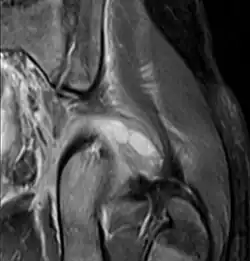

CT exam showing a multiloculated fluid collection in the left gluteus minimus muscle found to be a staph aureus pyomyositis in a 12-year-old healthy boy.

Coronal T2 weighted fat suppressed image showing a multiloculated fluid collection in the left gluteal musculature due to tropical pyomositis in a 12-year-old boy.